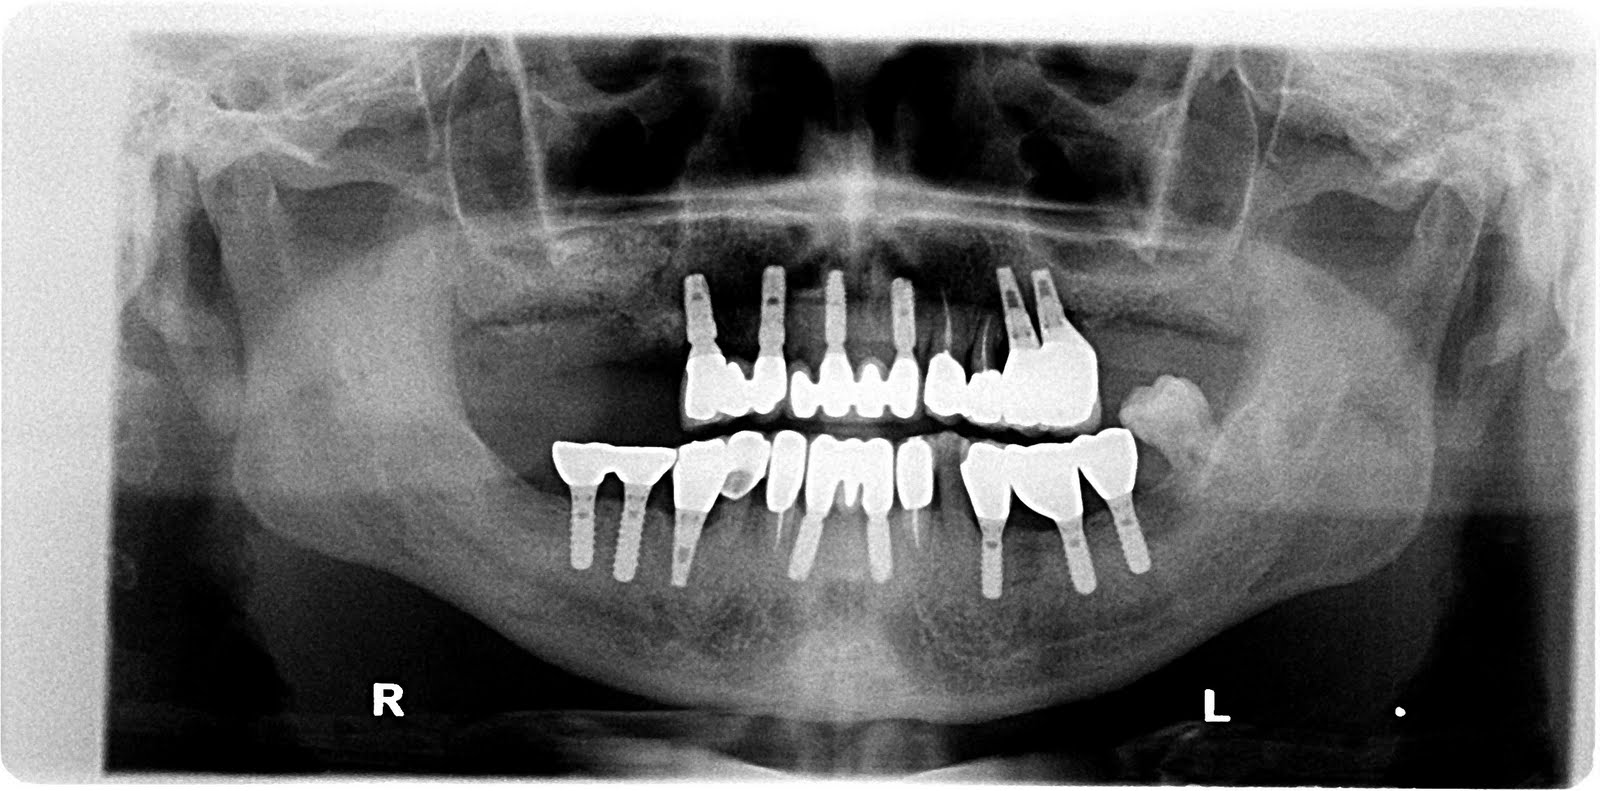

Dental Implant Sinus Membrane Perforation . Implant perforation of the maxillary sinus was defined as the intrusion of a dental implant into the sinus. Some early warning signs to watch out for include: A perforated sinus occurs when the implant penetrates the sinus membrane (schneiderian membrane), which separates the sinus from the upper jawbone. The aim of the present systematic review was to investigate the clinical outcomes after the perforation of the maxillary sinus by dental implants, or after maxillary. Sinus perforation after a dental implant can lead to serious complications if not detected early. The aim of this study was to estimate the incidence of sinus membrane perforation in maxillary sinus augmentation surgery using a lateral approach and the. A common complication of sinus augmentation is perforation of the sinus membrane during augmentation and/or implant placement. Perforation of the sinus membrane can result in dissemination of grafting material into the sinus cavity, potentially compromising.